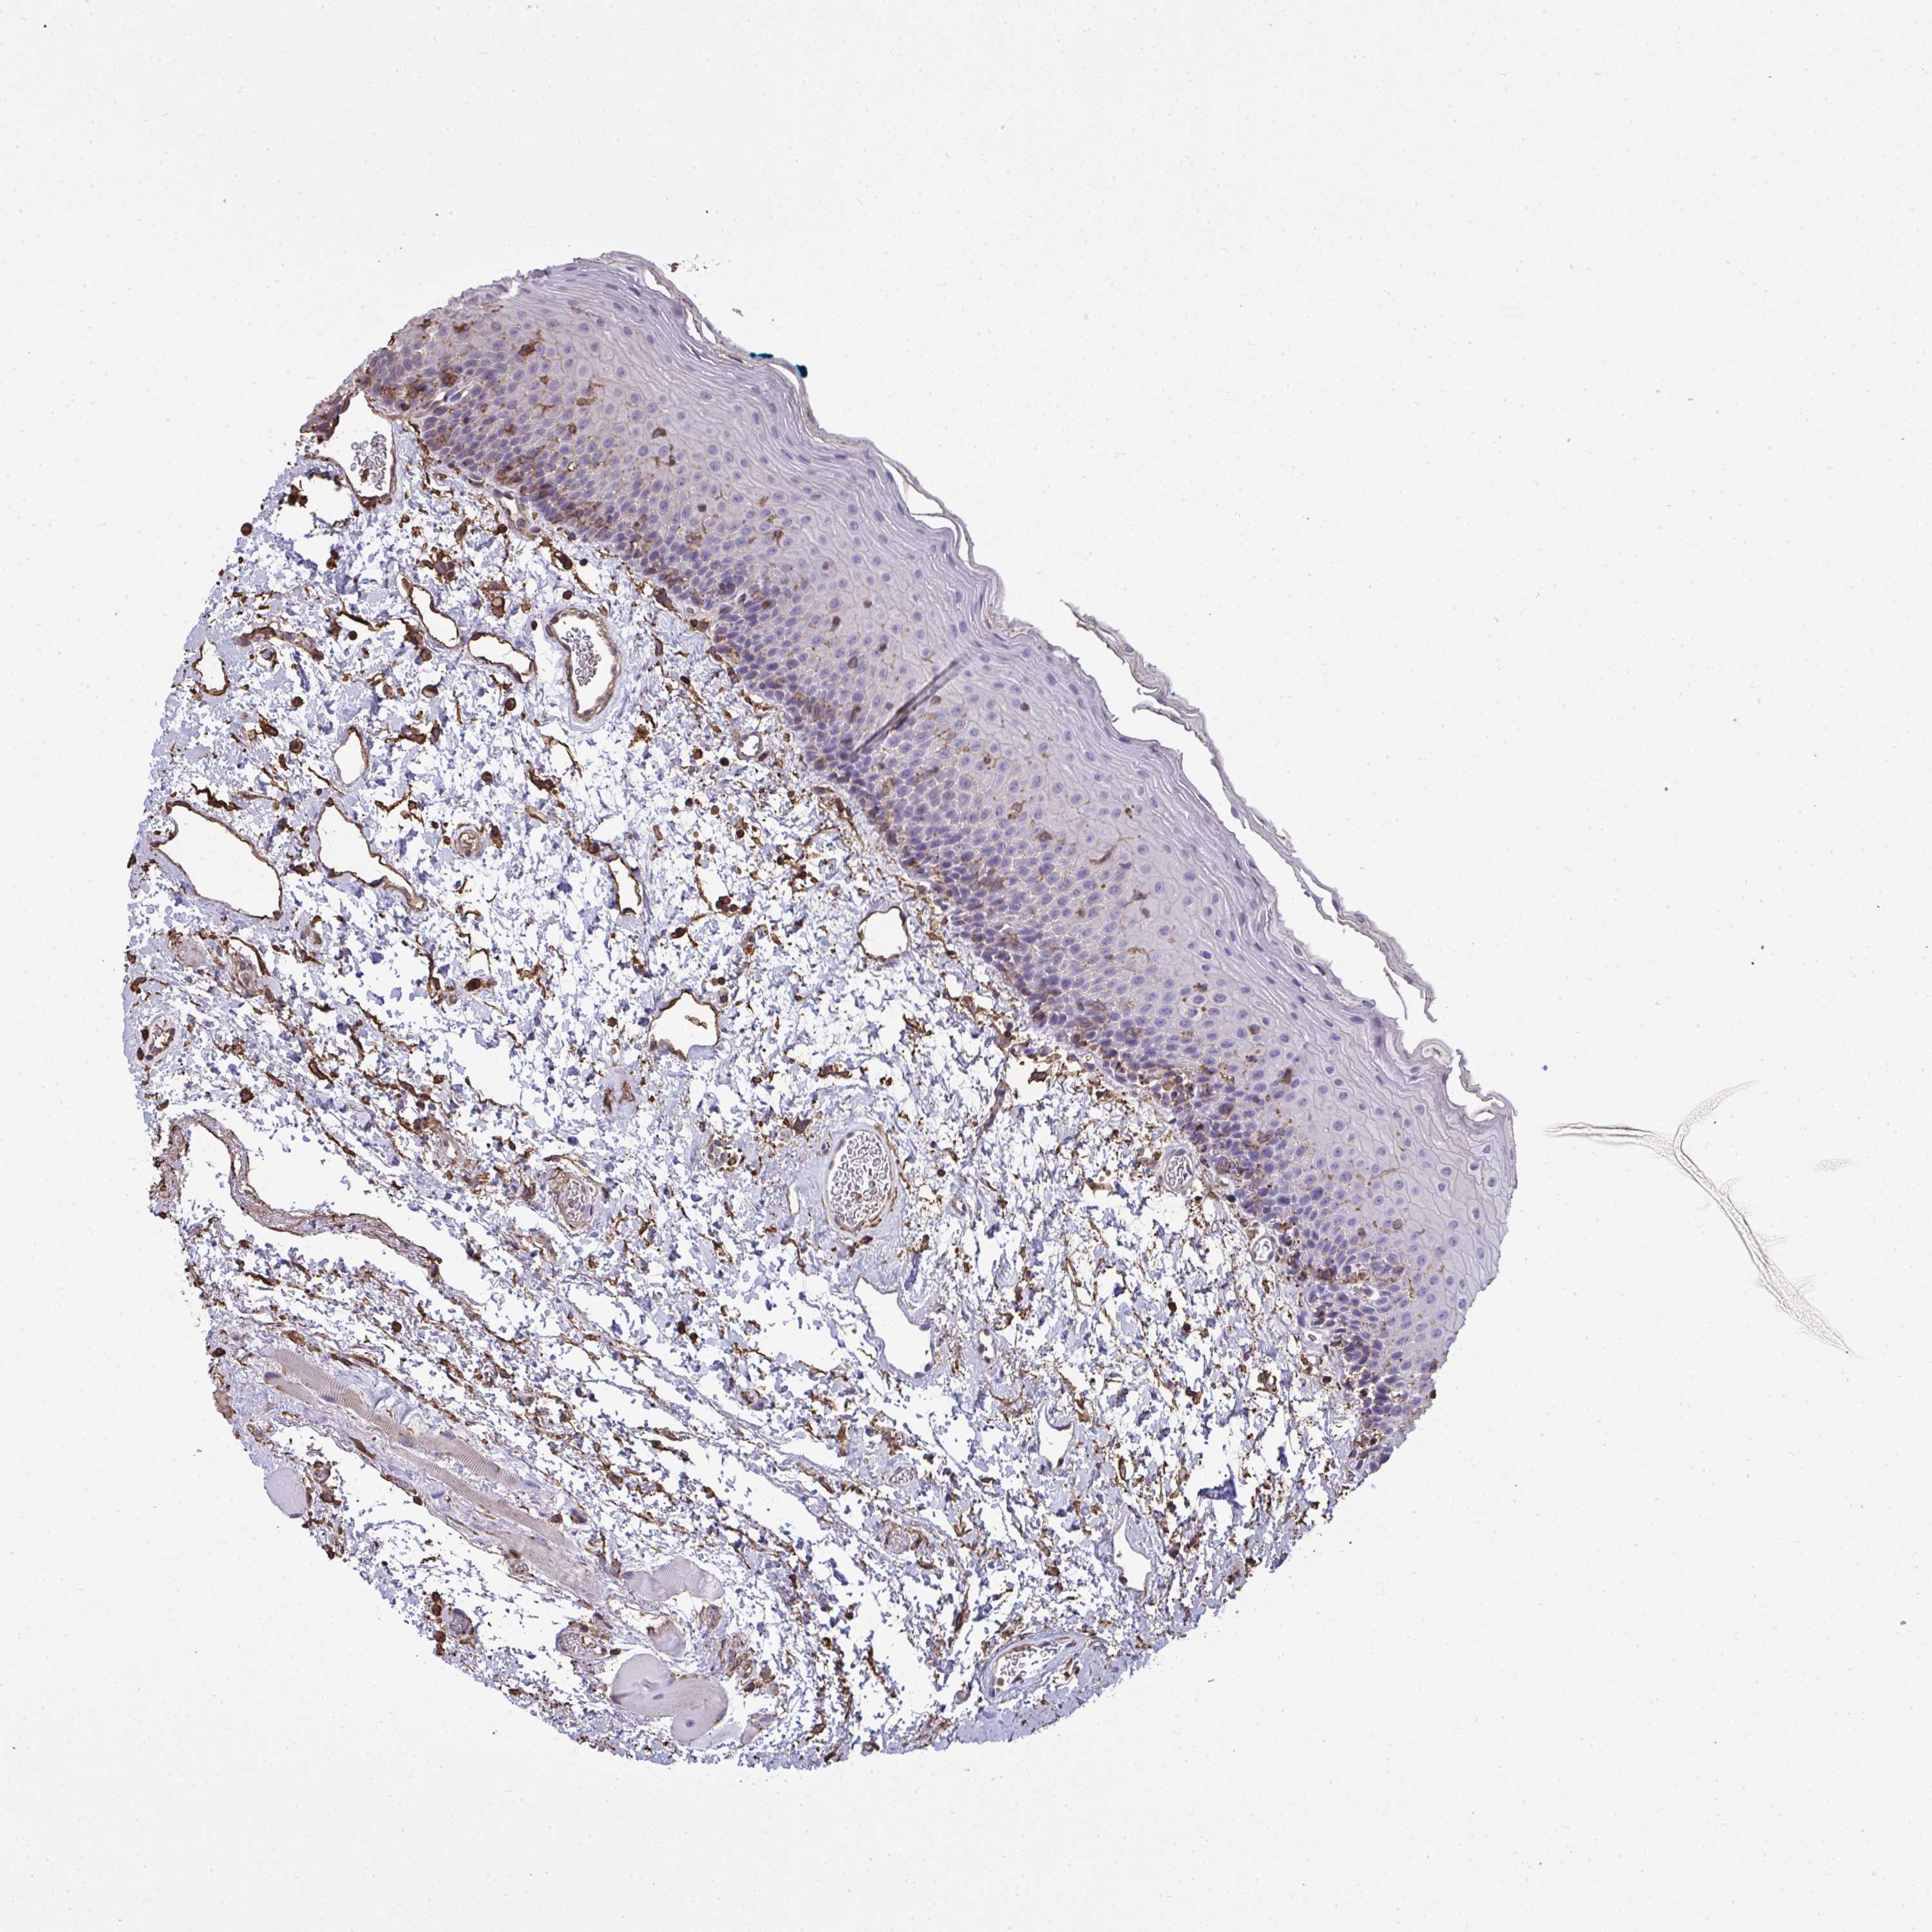

TISSUE PRIMARY DATA ORAL MUCOSA Show tissue menu

ORAL MUCOSA - Antibody stainingi

Antibody staining in the annotated cell types in the current human tissue is reported as not detected, low, medium, or high, based on conventional immunohistochemistry profiling in selected tissues. This score is based on the combination of the staining intensity and fraction of stained cells.

Each image is clickable and will lead to virtual microscopy that enables deeper exploration of all samples and also displays staining intensity scores, fraction scores and subcellular localization as well as patient and tissue information for each sample.

Antibody HPA035330Antibody CAB003677

Squamous epithelial cells Not detectedNot detected